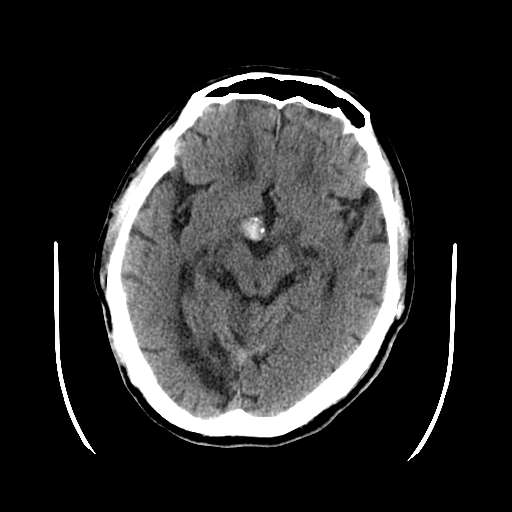

皮脑应该可以诊断,不知道增强病灶有没有强化(ct值),从片上看好像有轻度强化,定位像是脑外的,圆形高密度,内部有点状更高密度考虑为点状钙化,首先考虑为脑膜瘤.鉴别诊断:胶质瘤,垂体瘤,听神经瘤等.

这次病变主要是是因为脑干及小脑的梗塞,另外原有多发脑梗塞。右侧鞍上池及颞叶区可见一大部钙化的病灶,强化后略有增大,并见一条血管进入,考虑血管瘤。不排除脑膜瘤可能!~!

无占位,无水肿带,大部分钙化,av畸形?增强的图片都不尽量在同层面,难比较强化,如果有强化迹象肯定是av畸形!